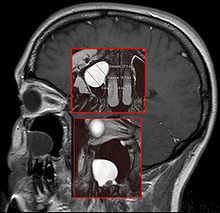

Big mucous membrane cyst in the right maxillary sinus (human skull)